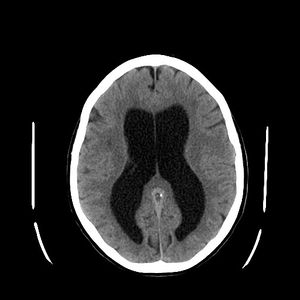

| استسقاء المخ كما يظهر في الأشعة المقطعية على المخ. المناطق السوداء في منتصف المخ هي تضخم غير طبيعي ومملوء بالسوائل. | |

- الأشعة المقطعية : وتعطي صور واضحة عن الحالة ومكان الانسداد.